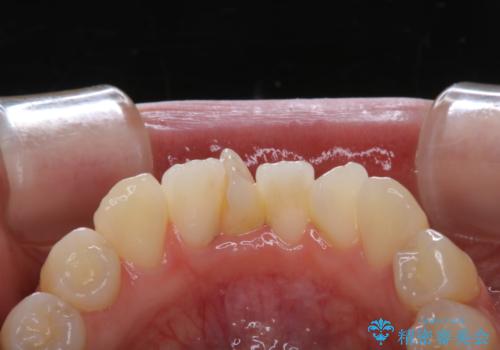

矯正治療開始前のPMTC

- 矯正カウンセリング、矯正検査後にクリーニング希望で来院されました。しばらく歯科医院にて、クリーニングを行ってなく、歯石やステインが気になるとのことでした。PMTC(自費クリーニング)30分コースを行いました。

矯正治療は、歯を動かすため歯ぐきにもかなりの負担がかかります。そのため歯列矯正の前にはしっかりとしたクリーニングを行い、歯ぐきのコンディションも整えることが大切です。また、歯石やステイン(着色)が歯についたままだと、矯正の装置が、適切に設置できなかったり、装置が外れやすくなってしまったりとトラブルの原因になることがあります。矯正治療中に歯周病や虫歯にならないためにも、専門的なクリーニングを行うことが大切です。